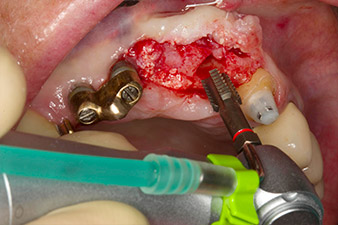

Enroscado mecánico del implante con el contra-ángulo WS-75 L

Imagen 4: Enroscado mecánico del implante con el contra-ángulo WS-75 L con una transmisión de 20:1 (programa P5).

Para compensar la pérdida de hueso periodontal y conseguir un resultado estético, el implante se combinó con una regeneración ósea guiada con material sustituto xenógeno y con una membrana de colágeno

(figuras 5 y 6).